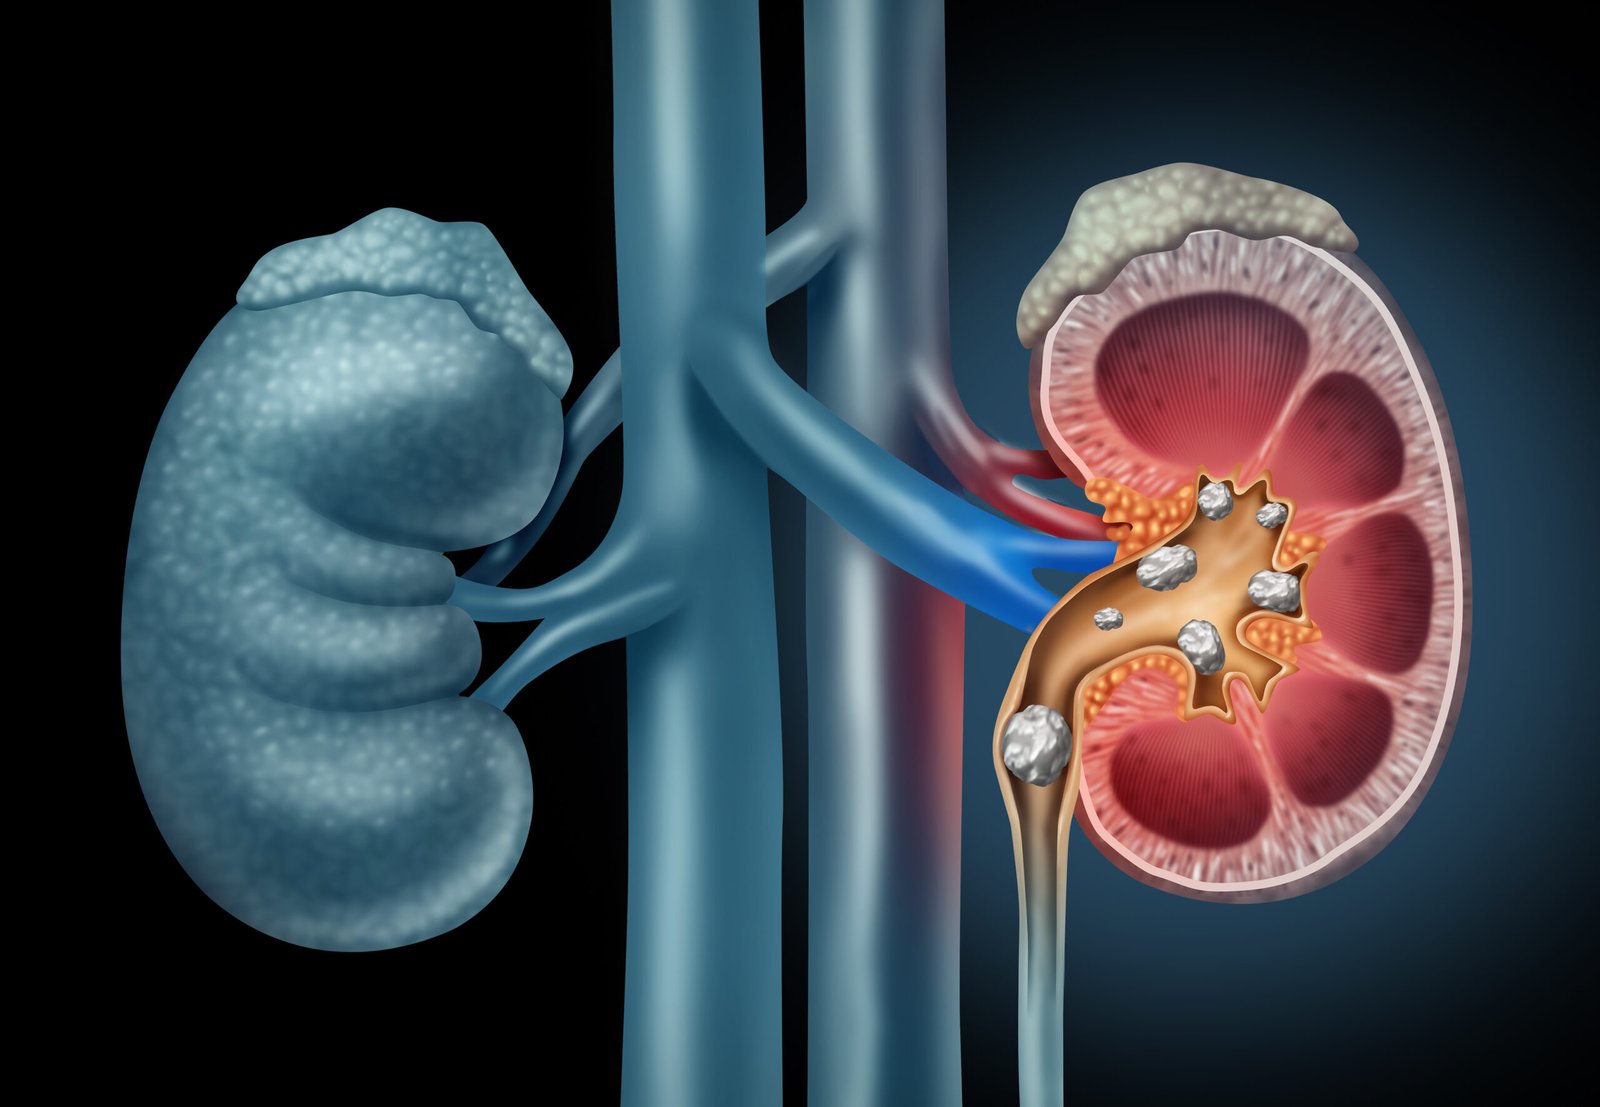

The process of forming stones in the kidney, bladder, and/or urethra (urinary tract) is called urolithiasis. Kidney stones are a common cause of blood in the urine and pain in the abdomen, flank, or groin.

The process of forming a kidney stone, a stone in the kidney (or lower down in the urinary tract). Kidney stones are a common cause of blood in the urine and pain in the abdomen, flank, or groin.

Formation of stone in the kidney is called nephrolithiasis.